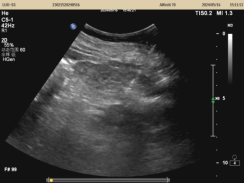

70岁的罗先生觉得左腰部不舒服有一段时间了,在几年前的体检中发现左肾有一个8.2x197.5px的囊肿,由于囊肿过大,医生建议手术治疗。因年龄偏大,担心手术风险,所以对手术治疗一直心存顾虑。他听说威远县人民医院超声科有不手术就可以治疗囊肿的方法,抱着了解的心态就来了。超声科副主任医师何玉周向罗先生详细解释了超声引导下经皮囊肿穿刺抽液硬化治疗术,并对其进行了囊肿硬化治疗。术前术后即刻对比,效果立竿见影,囊肿消失不见,罗先生避免了开放手术和腹腔镜手术,感到十分的满意。